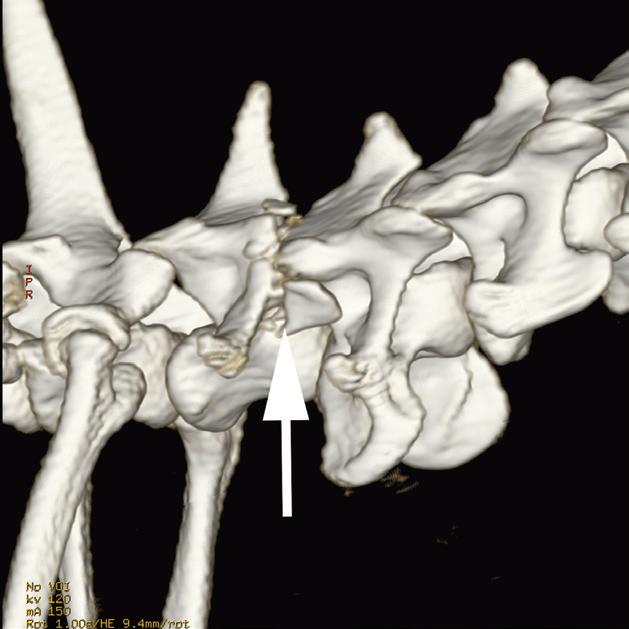

Rycina

3.2.8. Podwichnięcie kręgów szyjnych ze złamaniem wyrostka stawowego (pies) TK i MR

Badania wykonano u 5-letniej samicy mieszańca w typie teriera, która została pogryziona w okolicy szyjnej przez większego psa tego samego dnia, w którym wykonano badania. Podczas wizyty u psa zaobserwowano deficyty neurologiczne z neuroanatomiczną lokalizacją w obrębie C6–T2. Radiogramy przeglądowe ukazały grzbietowe podwichnięcie kręgu C7 względem C6 oraz zwężenie przestrzeni międzykręgowej C6–C7 (a – grot strzałki). Podobne zmiany uwidoczniono na obrazach TK w projekcji strzałkowej i 3D (b, f – grot strzałki). Dodatkowo stwierdzono wieloodłamowe złamanie z przemieszczeniem prawego doczaszkowego wyrostka stawowego kręgu C7 (c–e – strzałka). Dla porównania przedstawiono prawidłowy lewy wyrostek stawowy (f – strzałka). W badaniu MR przestrzeń międzykręgowa C6–C7 była zwężona i wykazywała obniżoną intensywność sygnału w obrazach T2-zależnych (i – strzałka), a przemieszczony materiał dyskowy znajdował się w prawej dobrzusznej części kanału kręgowego (g, h – grot strzałki). W obrazach występują cechy ucisku na rdzeń kręgowy (g–i) oraz zwiększona intensywność sygnału w sekwencji T2-zależnej w obrębie rdzenia na poziomie C6–C7 (h, i), co wskazuje na jego uszkodzenie wewnętrzne. Materiał dyskowy został chirurgicznie usunięty z kanału kręgowego, a podwichnięcie zredukowano i ustabilizowano operacyjnie